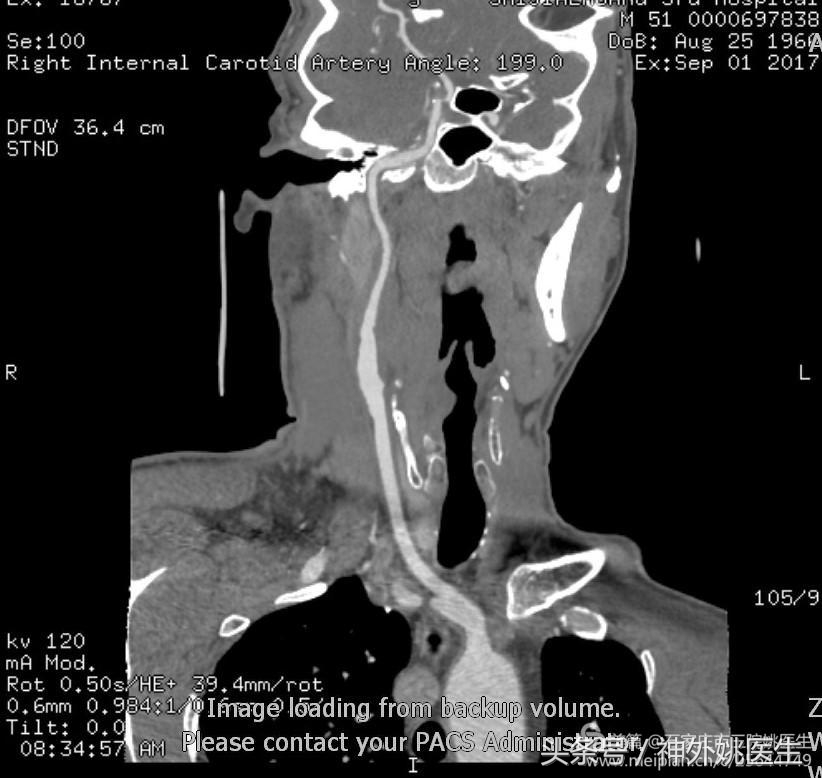

2.术后颈部CTA(图19):

图19 颈内动脉起始部狭窄消失,管径恢复正常。